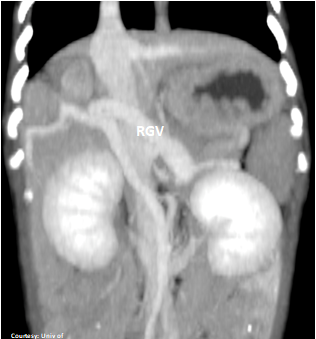

Does the RIGHT GASTRIC VEIN (RGV) contribute blood to the shunt?

WEISSE 2022